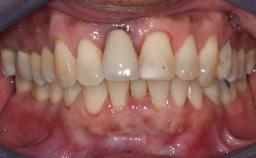

Missing Maxillary Central Incisor, Single Implant Replacement with Adjacent Tooth Restoration

The patient presented with a failing tooth-supported fixed dental prosthesis with cantilever extension replacing the right maxillary central incisor. His chief presenting complaint was poor esthetics, in particular the dark discolored margin around the abutment tooth, the maxillary left central incisor. He reported a history of trauma at a young age, which necessitated the replacement of his maxillary right central incisor as well as root canal therapy of the adjacent left central incisor. The existing prosthesis had been in situ for over 20 years. The initial periapical radiograph displayed good proximal bone levels at the adjacent teeth and a wide incisive canal, which was a concern. The left central incisor presented a very wide root canal treatment with compromised radicular dentin thickness, which was a consideration in the decision between a new tooth-supported fixed dental prosthesis vs. an implant-supported prosthesis. After a lengthy discussion on the risks and benefits of both treatment options, the patient decided on a single-tooth implant replacement.